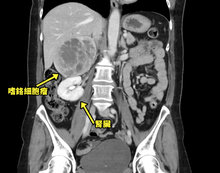

52歲林女士本身有輕微的高血壓,經規律服藥控制良好,雖偶有胸悶、心悸等情形,但因發作時間短暫,不以為意;日前,林女士心悸再次發作且伴隨嚴重盜汗及發燒,被家人送往台北慈濟醫院急診。抽血檢查發炎指數為4(正常為1以下),懷疑腫瘤的可能,進一步檢測神經內分泌腫瘤指數,竟比正常值高出近9倍;經斷層掃描發現,林女士的腎上腺有一顆10公分的罕見嗜鉻細胞瘤,腫瘤已幾乎要比腎臟還大。